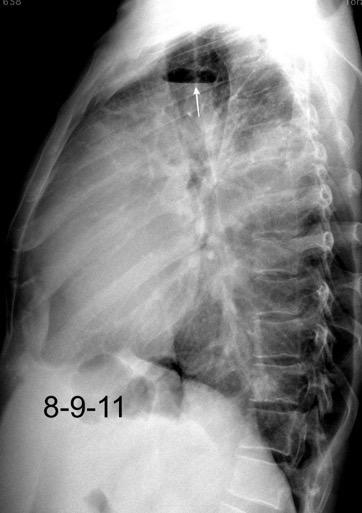

Marzo 2014: Perforación longitudinal distal secundaria a episodio de vómito (síndrome de Boerhaave). Derrame pleural izdo. que evoluciona a empiema.

Wang C-T et al. Tension hydropneumothorax in a Boerhaave syndrome patient: A case report . World J Emerg Med, 2021. Katabathina V et al. Nonvascular, nontraumatic mediastinal emergencies in adults:a comprehensive review of imaging findings. Radiographics. 2011.